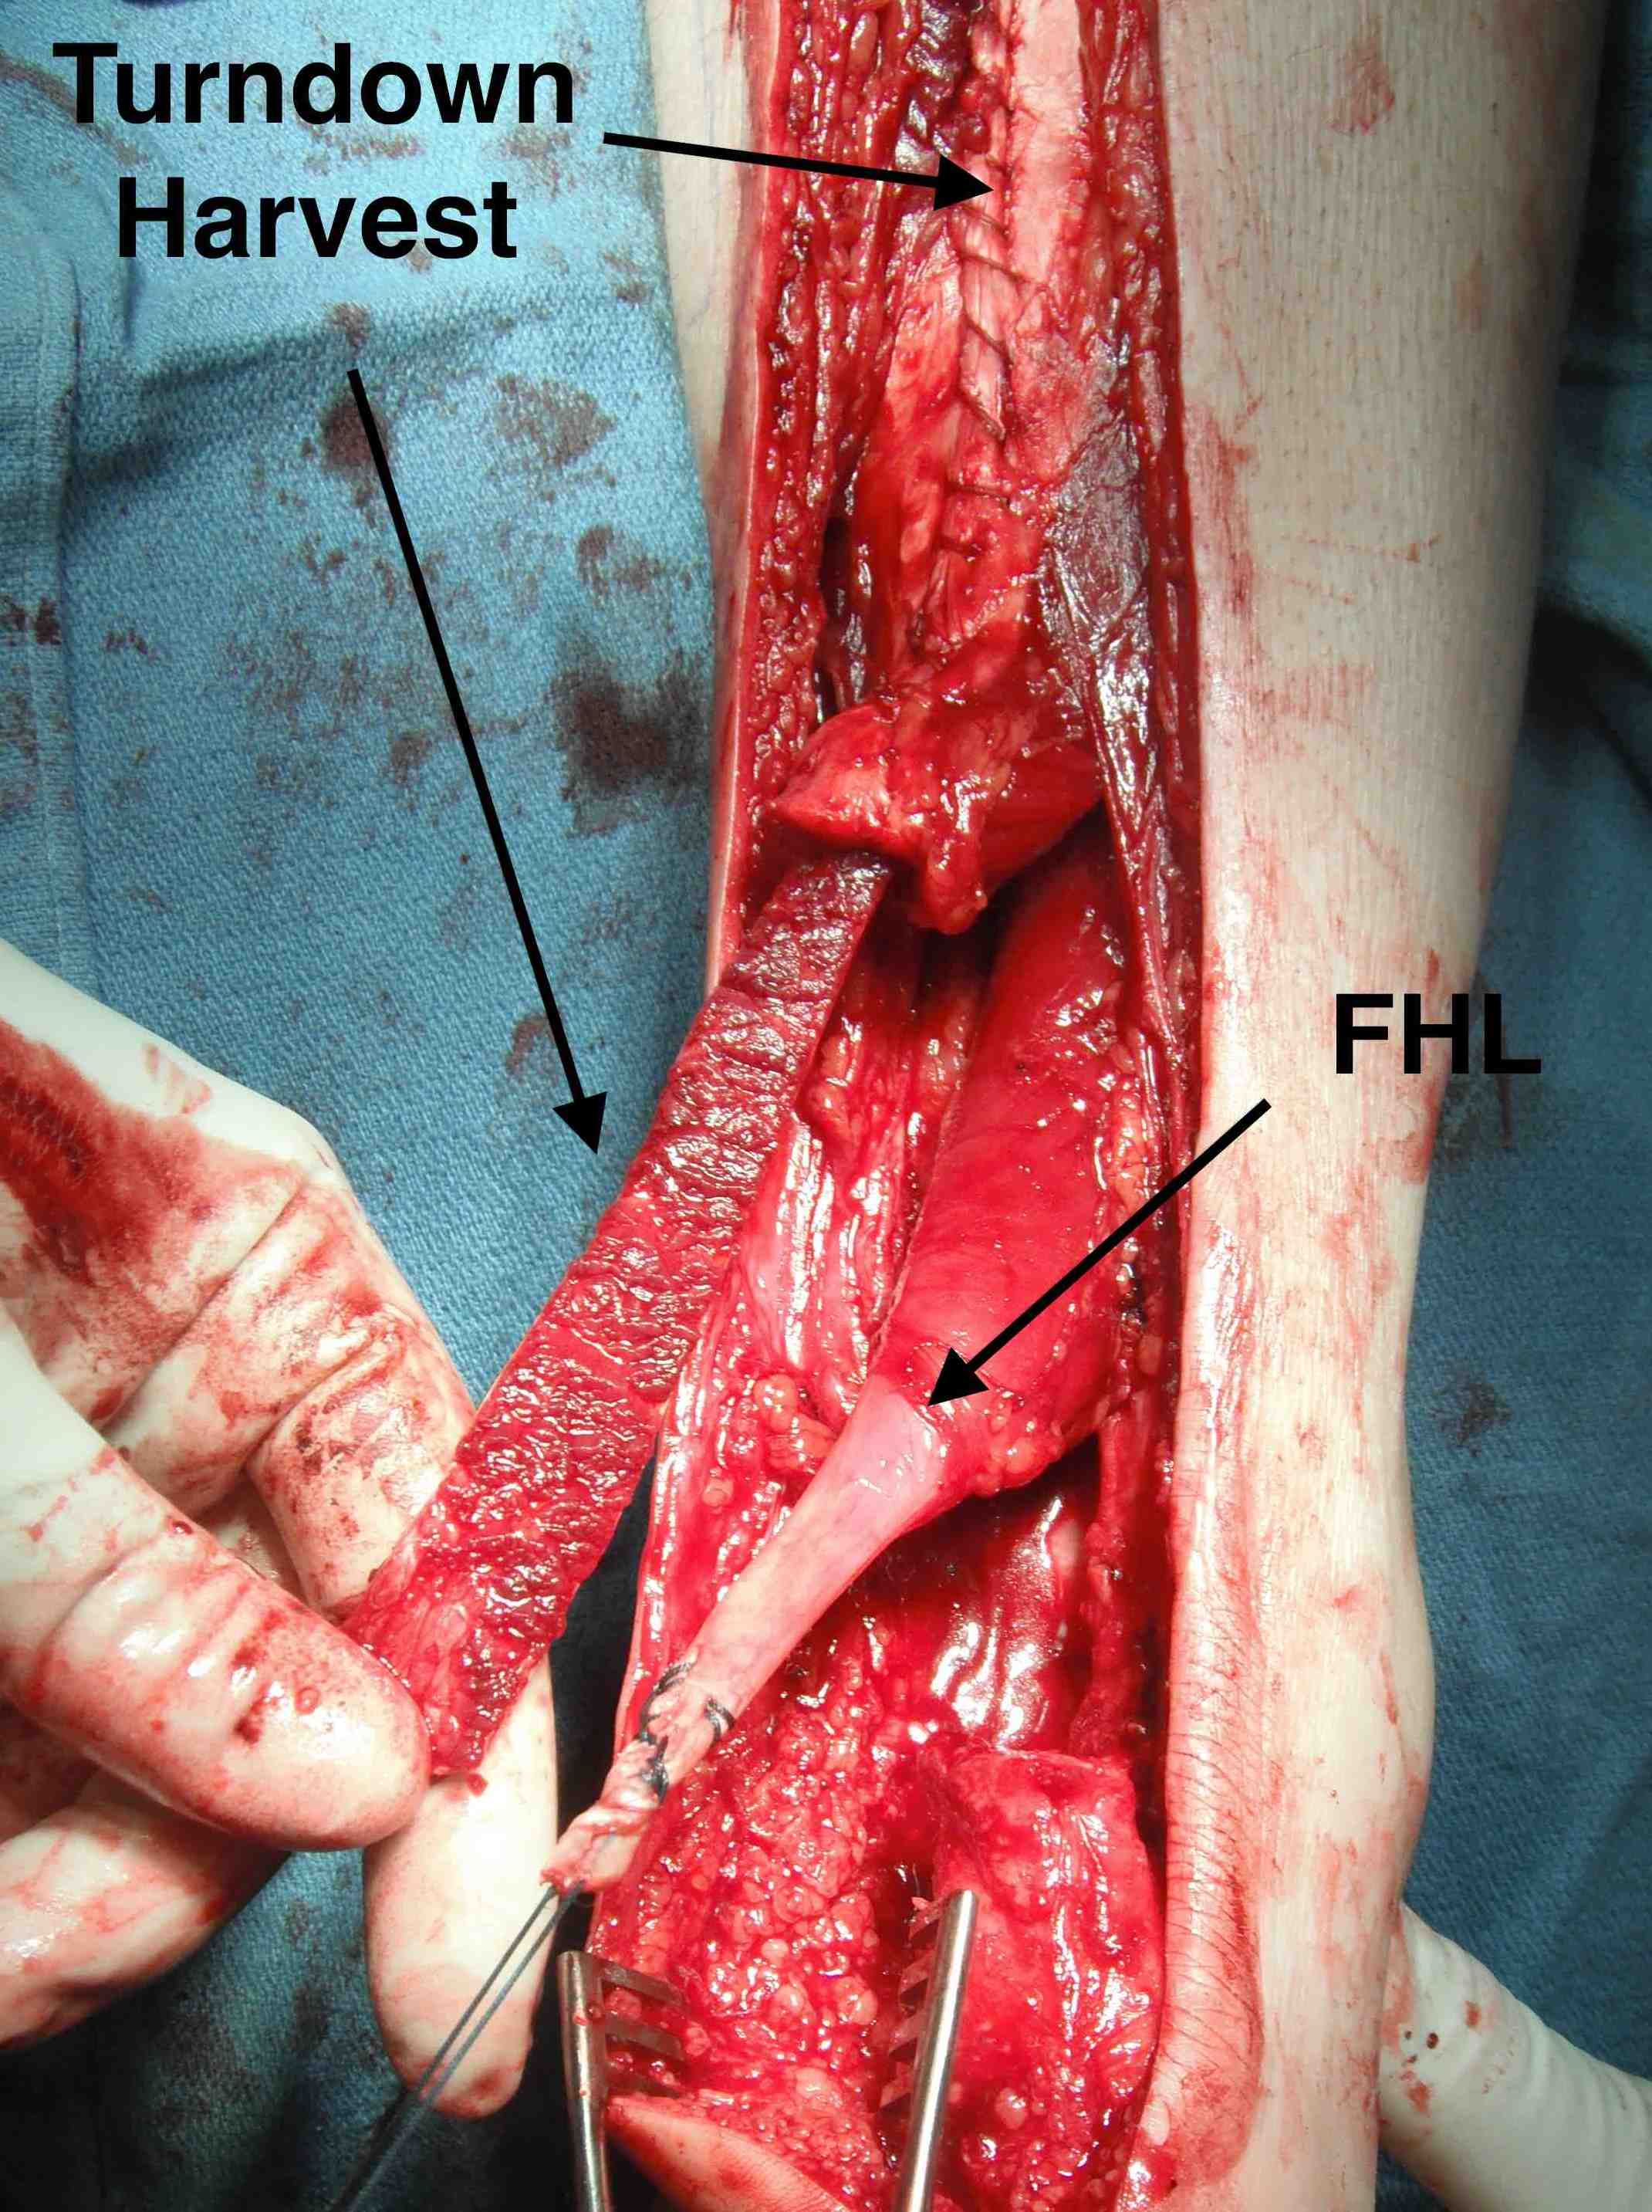

VY lengthening

Technique

Vumedi VY lengthening + FHL transfer video

Turndown + FHL transfer with FHL passed through a transverse tunnel in the calcaneum

FHL transfer

Technique

Vumedi VY lengthening + FHL transfer video 1

Vumedi VY lengthening + FHL transfer video 2

Identify FHL tendon medially

- identify and protect tibial nerve

- pull tendon through and transect with sufficient length

- through drill hole in calcaneum and secure